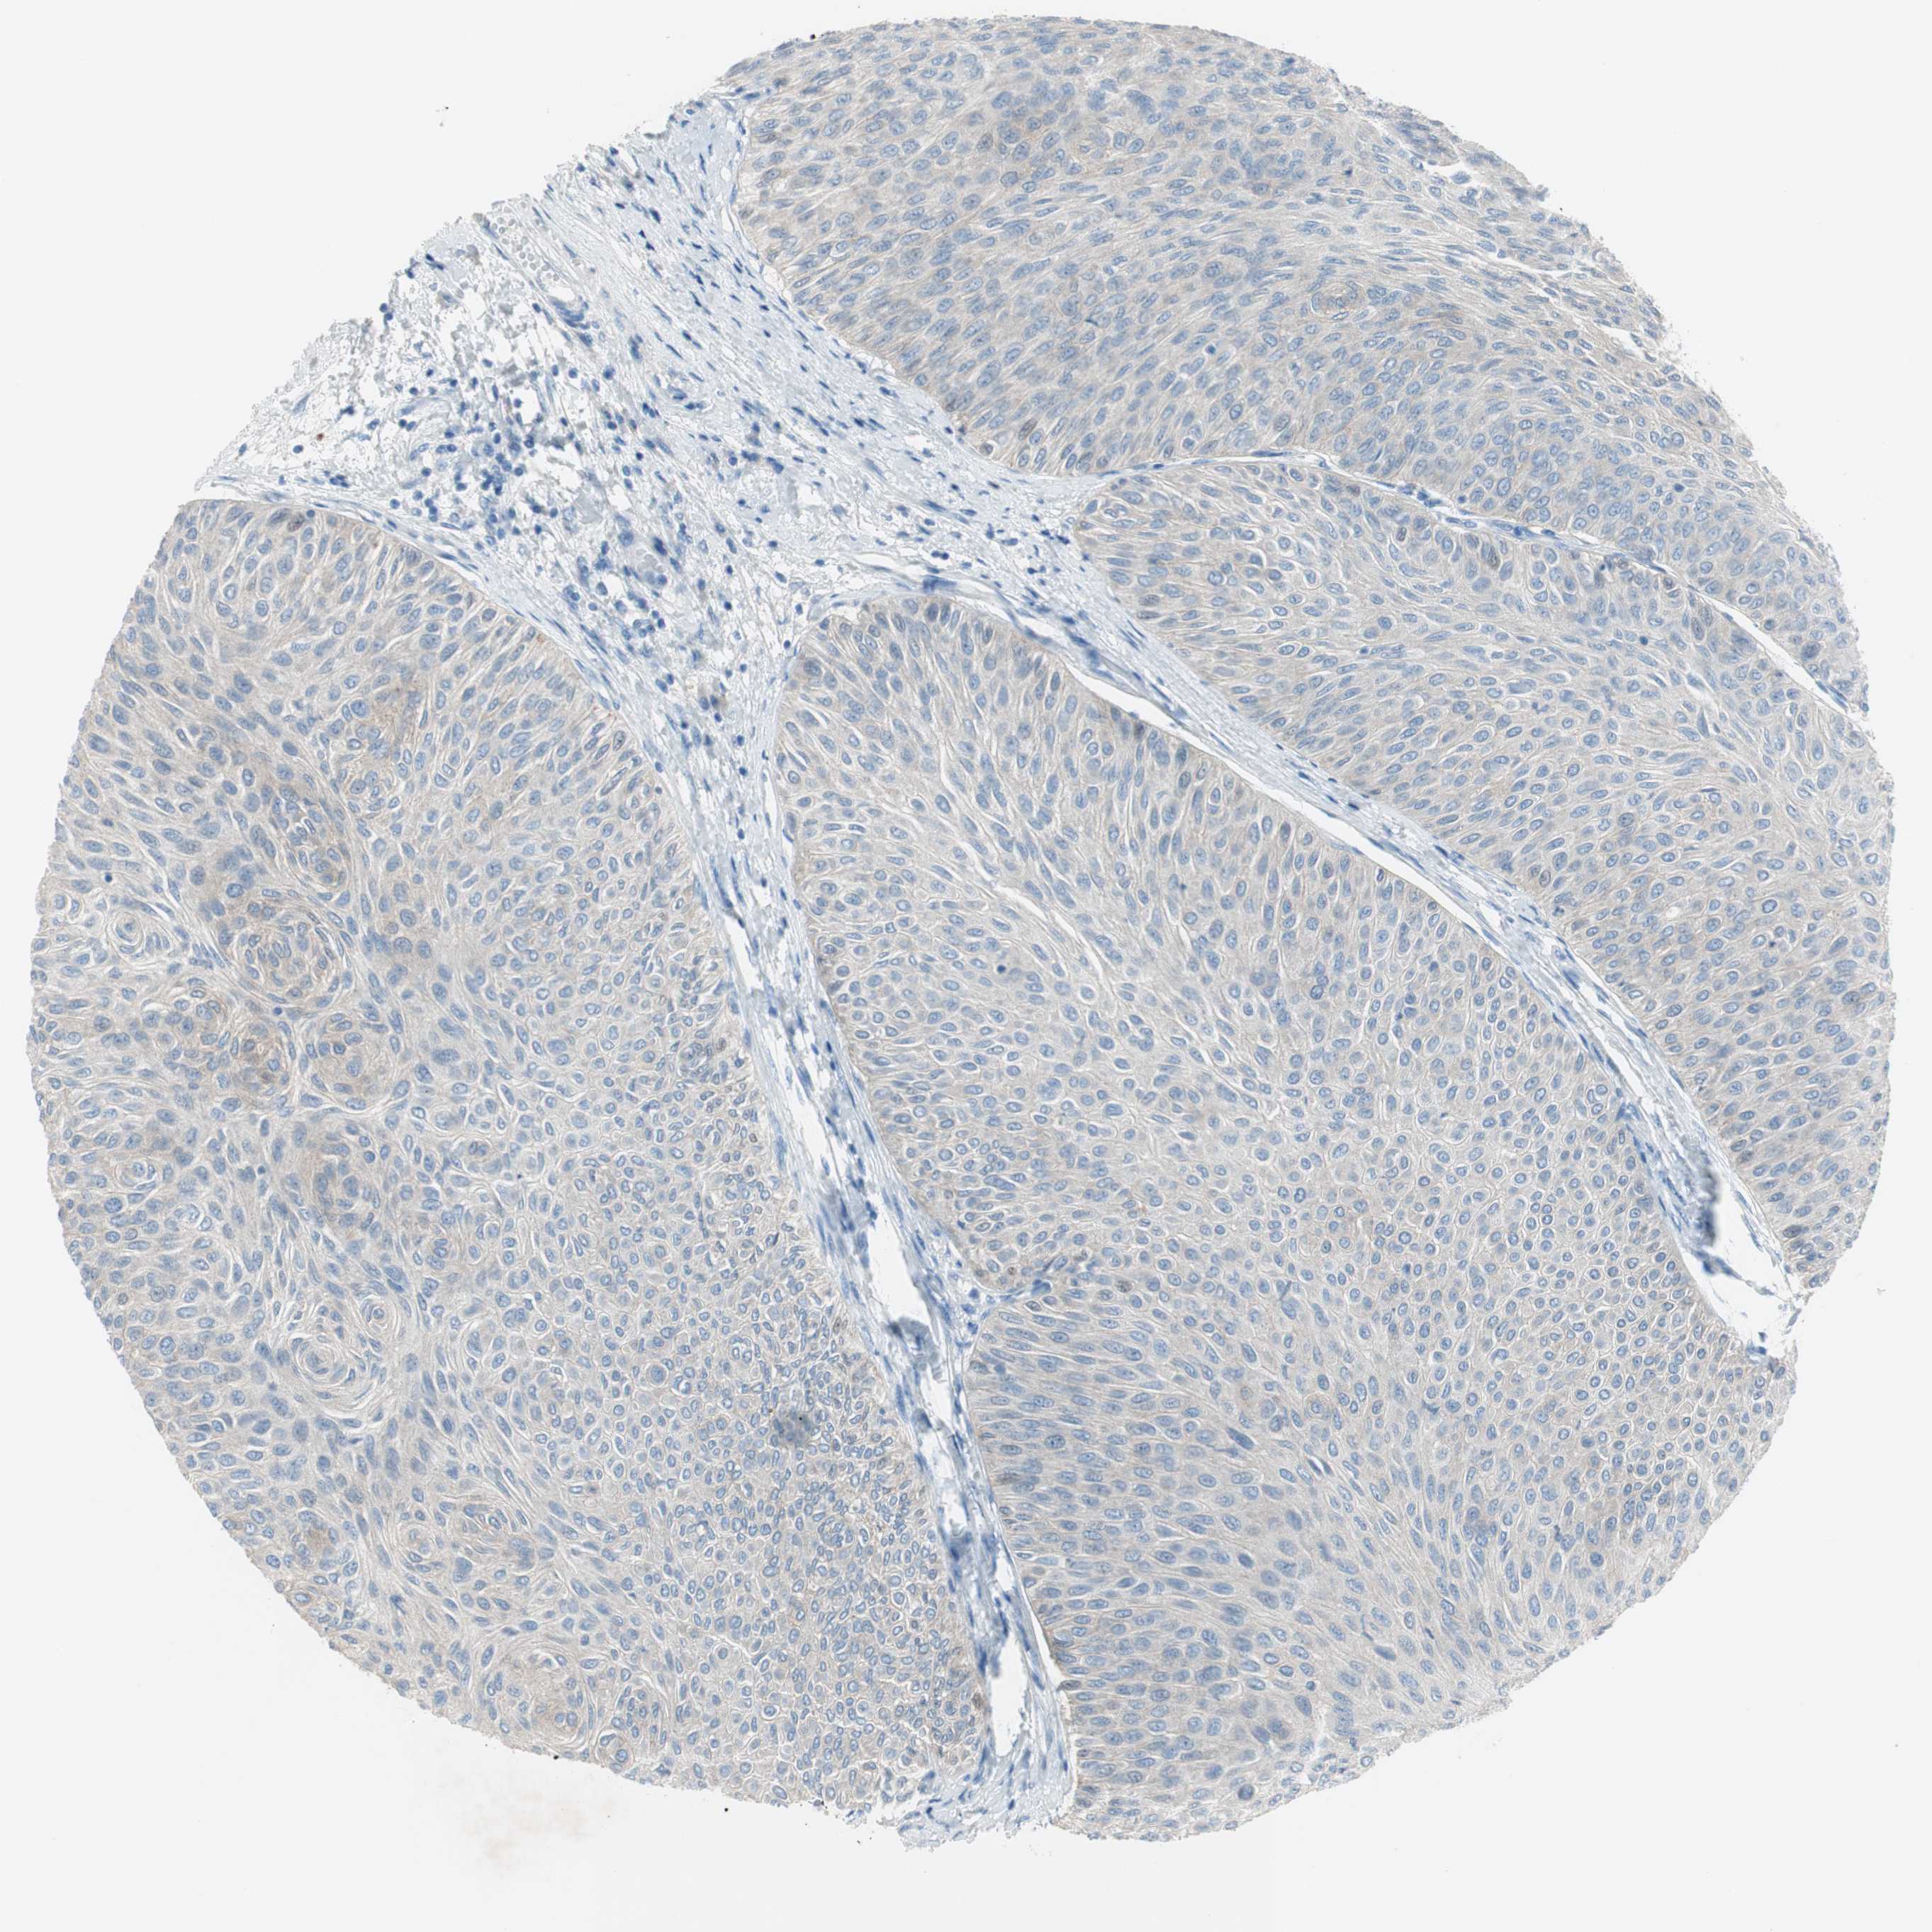

UROTHELIAL CANCER - Protein expressioni

A mouse-over function shows sample information and annotation data. Click on an image to view it in a full screen mode. Samples can be filtered based on level of antibody staining by selecting one or several of the following categories: high, medium, low and not detected. The assay and annotation is described here.

Note that samples used for immunohistochemistry by the Human Protein Atlas do not correspond to samples in the TCGA dataset.

Antibody stainingi

Antibody staining in the annotated cell types in the current human tissue is reported as not detected, low, medium, or high, based on conventional immunohistochemistry profiling in selected tissues. This score is based on the combination of the staining intensity and fraction of stained cells.

Each image is clickable and will lead to virtual microscopy that enables deeper exploration of all samples and also displays staining intensity scores, fraction scores and subcellular localization as well as patient and tissue information for each sample.

Antibody HPA009040

Antibody HPA024566

Staining

High

Medium

Low

Not detected

Intensity

Strong

Moderate

Weak

Negative

Quantity

>75%

75%-25%

<25%

None

Location

Nuclear

Cytoplasmic/membranous

Cytoplasmic/membranous,nuclear

Urothelial carcinoma, High grade

Urothelial carcinoma, Low grade